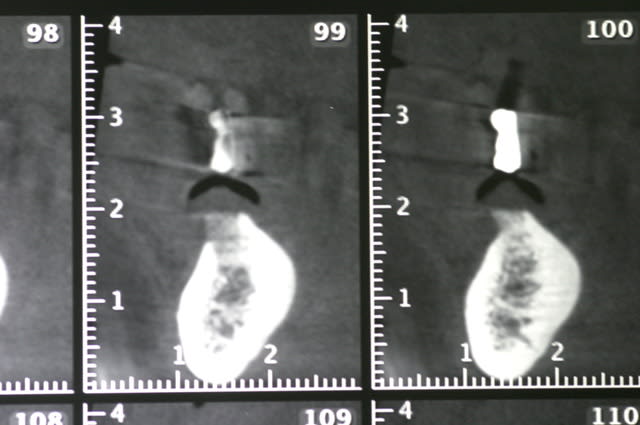

voici quelques images (de mauvaises qualités..désolé) d'un cone beam.

à la base le plan de traitement consistait en la pose de cinq implants et d'un bridge sur pilotis. mais dans le secteur mandibulaire gauche, il me semble que le NDI montre une anatomie un peu bizare. c'est mes yeux ou bien...?

non, ce type d'image est finalement assez fréquente.

dans plus de 25 % des cas tu trouvera des canaux supplémentaires à ton NAI.

le trucl étant d'éviter le principal canal. pour les autres canaux, il faut prévenir le patient qu'il peut y avoir quelques petites douleurs (pour toi ce sera juste un peu de stress...